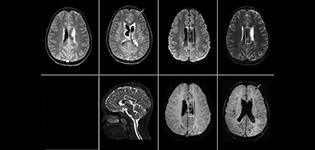

The value of susceptibility weighted imaging in visualizing brain injury is well documented. The Philips multi-echo SWIp technique provides fast susceptibility weighted imaging with enhanced susceptibility contrast and high resolution.

“Pediatric imaging is not without its challenges,” Dr. Miller says. “Since our patients are often very small, we need very high-resolution imaging. In cases of brain injury, we need to obtain information quickly so the treating clinicians can make decisions on care. We rely on high resolution and robust imaging capabilities, and SWIp provides that.”

“SWIp helps us identify blood or blood products, calcification, and diseases that affect the vascular system,” says Dr. Miller. “In children with traumatic brain injuries, it highlights areas that are injured, better than some of the previous techniques that we were using. These children often have micro-injuries that cause small amounts of blood or tissue damage. Adding SWIp helps us to better characterize the extent and nature of the injury. Having characterized an injury to the extent of what’s possible supports our diagnostic confidence.”

“I would definitely recommend other users to implement SWIp. We initially added the SWIp sequence following a lot of support for its utility in the literature. Then we directly compared SWIp to the 2D gradient echo sequences that we were using. After a good amount of clinical experience in seeing its benefits, we were confident to replace the old sequences with SWIp. It gives us a better assessment of the physiological processes of the brain that were less apparent on our previous imaging sequences,” says Dr. Miller. “SWIp is now a routine sequence for imaging traumatic brain injury patients at PCH, and it’s episodically added for patients who have intracranial vascular abnormalities.”

“I believe SWIp is rapidly becoming the standard in imaging traumatic brain injury, because of its high sensitivity to venous blood products. SWIp may even help attract patients; our neurosurgeons often ask to have the patients imaged on our scanners with highly sensitive techniques like SWIp. There’s also a growing application of SWI sequences in other vascular abnormalities because of the possibilities around physiological assessment of the brain than just a standard structural imaging.”